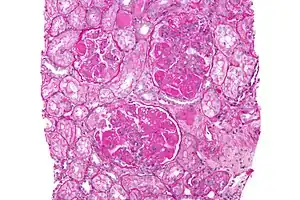

Diffuse proliferative glomerulonephritis (DPGN) is a type of glomerulonephritis that is the most serious form of renal lesions in SLE and is also the most common, occurring in 35% to 60% of patients.[1] In absence of SLE, DPGN pathology looks more like Membranoproliferative glomerulonephritis

In DPGN Most of the glomeruli show endothelial and mesangial proliferation, affecting the entire glomerulus, leading to diffuse hypercellularity of the glomeruli, producing in some cases epithelial crescents that fill Bowman's space. When extensive, immune complexes create an overall thickening of the capillary wall, resembling rigid "wire loops" on routine light microscopy. Immune complexes can be visualized by staining with fluorescent antibodies directed against immunoglobulins or complement, resulting in a granular fluorescent staining pattern. Electron microscopy reveals electron-dense subendothelial immune complexes (between endothelium and basement membrane). In due course, glomerular injury in DPGN gives rise to scarring (glomerulosclerosis). Most of SLE patients with DPGN have hematuria with moderate to severe proteinuria, hypertension, and renal insufficiency.[2]

A kidney biopsy is the most important diagnostic tool. With a biopsy, the sample will be looked at histologically. With this information, a proper diagnosis can be completed. There are many forms of glomerulonephritis, but under a microscope, DPGN will show increased cell count of polymorphonuclear cells, cellular crescents, and fibrinoid necrosis. A patient with DPGN will have more than 50% of their glomeruli involved.[4][5] If a patient has DPGN, that means they have an active form of glomerulonephritis.[10]